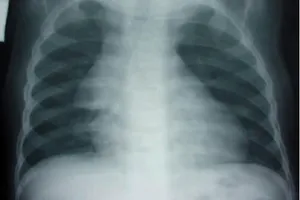

- Рентгенографию. Применяется кардио-тимико-торакальный и вазокардиальный индекс. Если объемы вилочковой железы превышают установленную норму, то на рентгене тень тимуса будет превышать пределы тени сердца и сосудистого пучка.

В детской эндокринологии стадию развития тимомегалии выявляют методом специальных измерений и по внешнему состоянию вилочковой железы, согласно показаниям рентгенограммы.

Для диагностирования тимомегалии у ребенка применяют кардиотимикоторакальный индекс (КТТИ). Этот показатель рассчитает доктор, опираясь на показания рентгенограммы. Необходимо измерить отношение площади сосудистого пучка в районе раздвоения трахеи на размер грудной полости в районе диафрагмы.

Также в детской эндокринологии есть вариант выявления стадии болезни, ориентирующийся на площадь тени железы, которую есть возможность зафиксировать рентгеном.

Условно у человека существует три анатомические части грудной клетки. Степень тимомегали у больного ребенка обуславливается тем, которую область детской грудной клетки затрагивает уровень разрастания вилочковой железы.

Выделяют следующие степени разрастания тимуса:

- 1 степень. Показатель ККТИ в пределах 0,33-0,37 единиц, вилочковая железа в области верхней трети грудной клетки.

- 2 степень. Показатель ККТИ в пределах 0,37-0,42 единиц, орган занимает область не более 2/3 детской грудной клетки.

- 3 степень. Показатель ККТИ выше 0,42 единиц, железа занимает площадь 2/3 и более области грудной клетки.

При установлении тимомегалии с помощью рентгенодиагностики должно учитываться, что стандартно теневая видимость тимуса не выходит за предел теневой проекции сердца ребенка и сосудистого пучка. Такое положение касается детей разного возраста.

Самым основным диагностическим способом увидеть увеличенный тимус всё ещё остаётся рентген. На нём можно увидеть признаки увеличения тимуса от первой до третьей степени. Однако не всегда увеличение бывает типичным, и требуются дополнительные снимки, кроме обзорного рентгена грудной клетки.